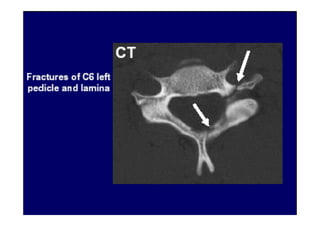

• 2. Tomografia Computadorizada

Está indicada no estudo de doenças ósseas,

sendo imagens que revelam espondilose e

osteófitos nas articulações zigoapofisárias.

É útil para medida do canal vertebral e o

forame de conjugação.

Observam-se imagens patológicas em

pacientes assintomáticos .